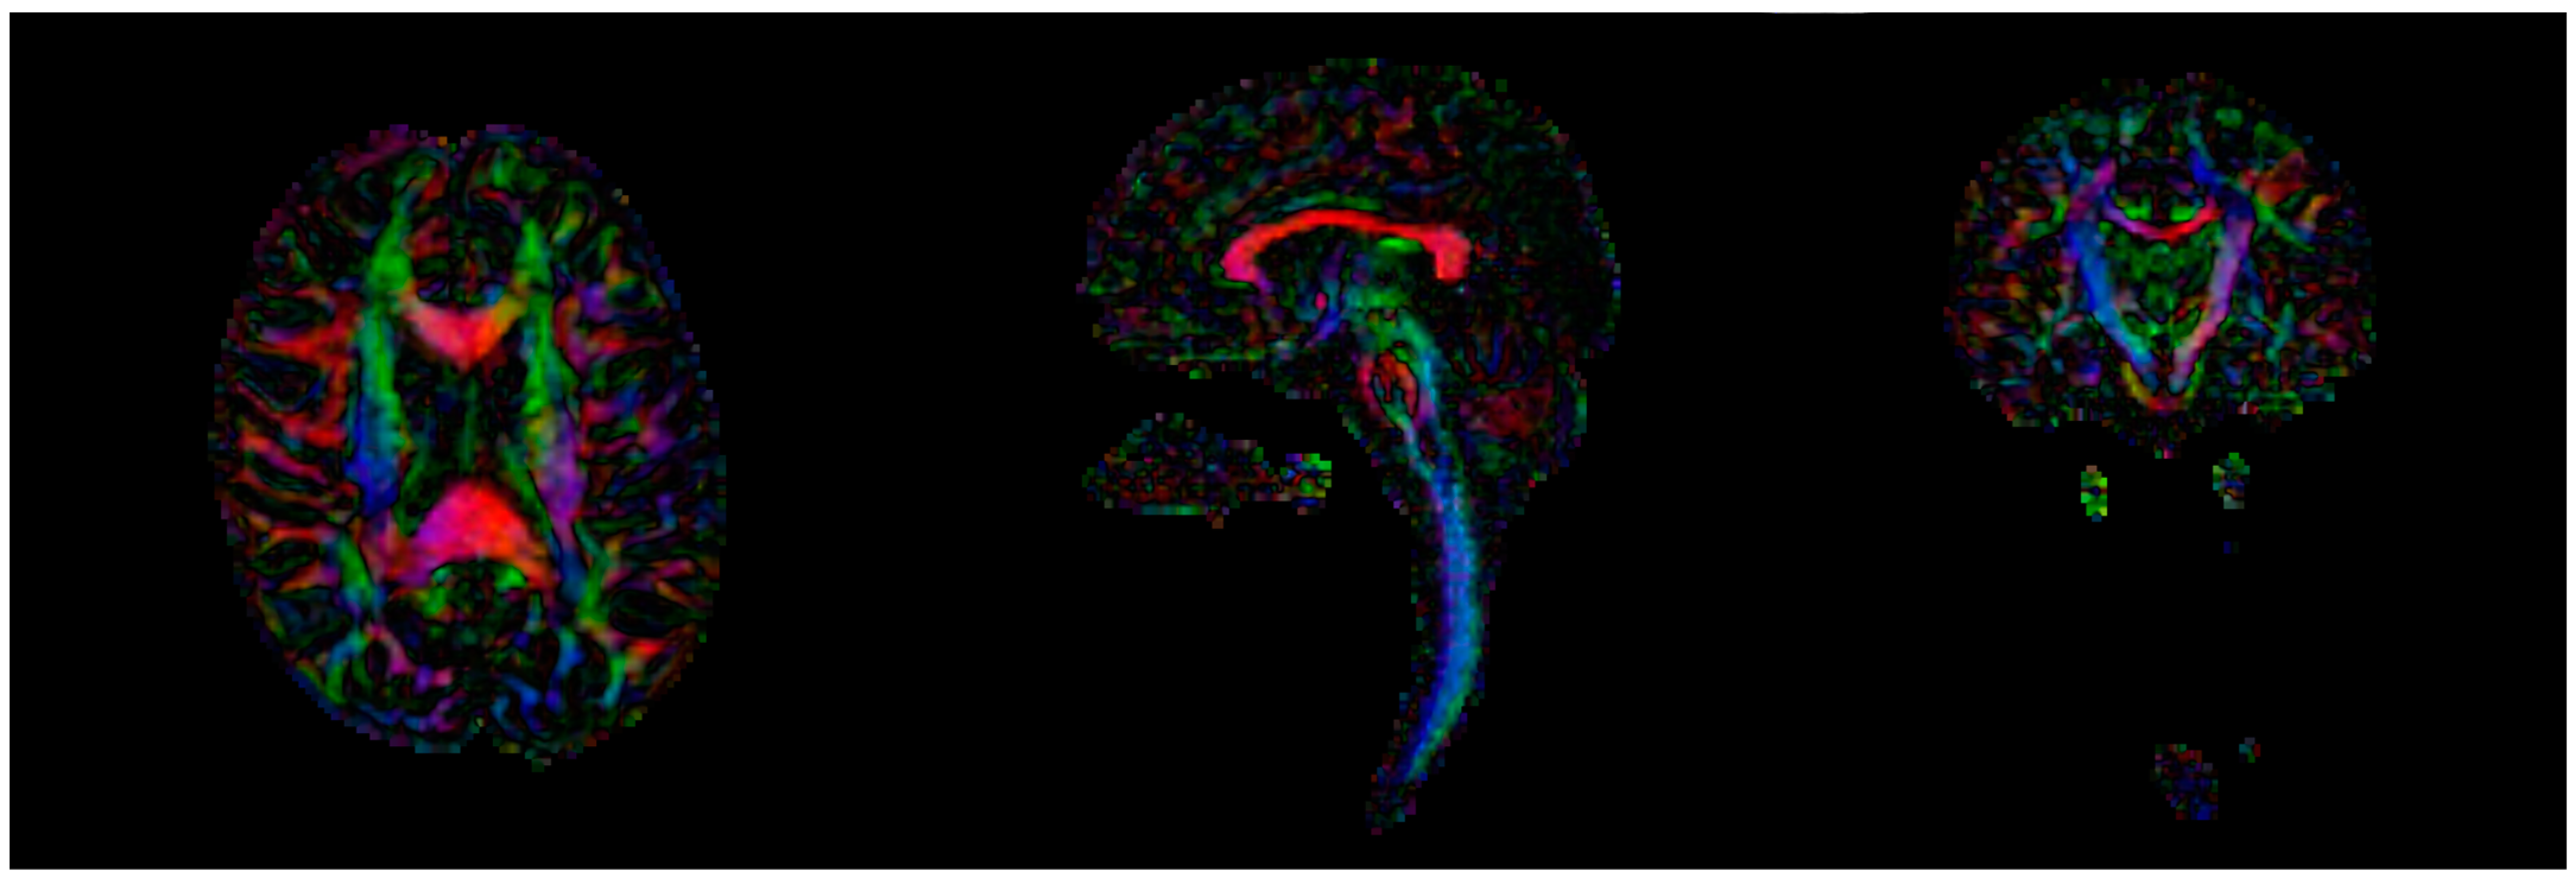

2.1. Magnetic Resonance Imaging (MRI)

2.1.1. Image Processing

2.1.2. Connectomics

| T1 | dMRI | |

| Sequence type | Turbo field echo | Diffusion-weighted single shot spin echo |

| Repetition time | 8.1 ms | 9000 ms |

| Echo time | 3.7 ms | 86 ms |

| Flip angle | 8° | 90° |

| Echo train length | 170 | 59 |

| No. of slices | 240 | 140 |

| B-value | - | 1000 s/mm2 |

| No. of gradient directions | - | 61 |

| Orientation | Sagittal | Axial |

| Acquisition duration | 359 s | 696 s |